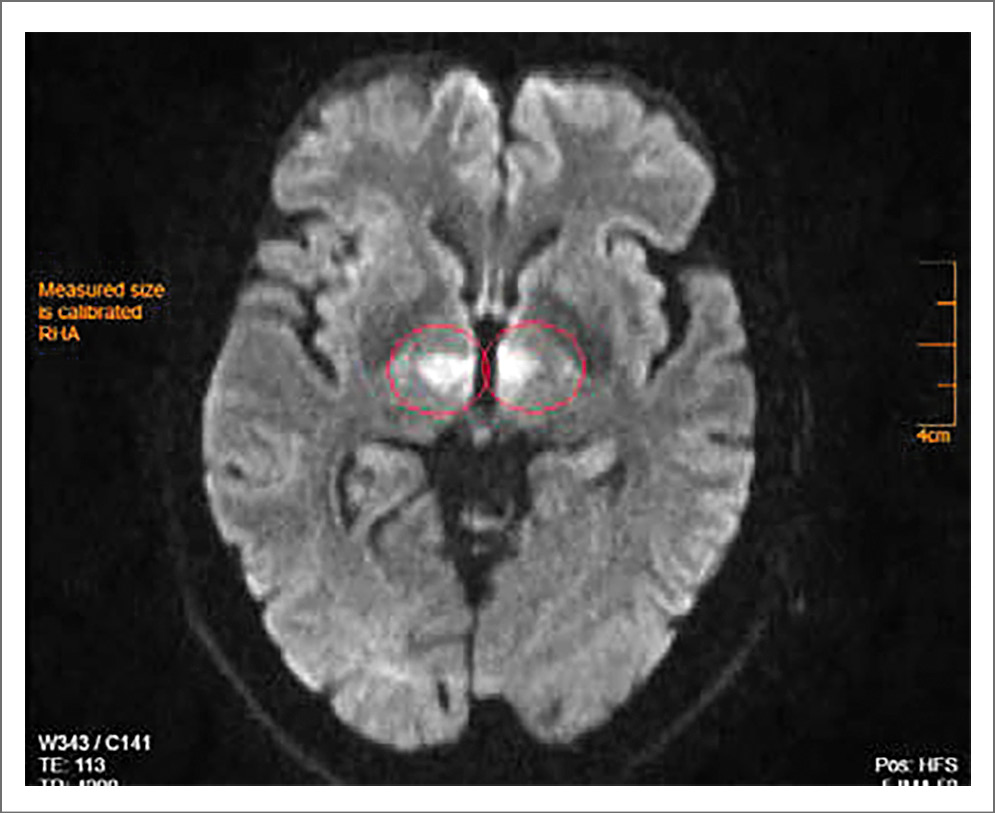

Состояние больной через 1 ч после поступления в стационар ухудшилось, в течение нескольких минут наросла общемозговая симптоматика до комы. На экстренной магнитно-резонансной томографии (МРТ) ГМ, выполненной по программе head general SE, TSE, TOF, TIRM c толщиной срезов 1, 4, 5 мм в аксиальной, сагиттальной и фронтальной проекциях с 3D-реконструкцией виллизиева круга без внутривенного контрастного усиления, обнаружены очаги острейшей ишемии в области таламусов с обеих сторон в бассейне таламоперфорирующих артерий размерами 1,0×1,2 см справа и 1,1×0,9 см слева. На времяпролетной МР-ангиографии виллизиева круга МР-сигнал от обеих задних мозговых артерий в сегменте P1 ослаблен. Признаки сосудистой мальформации и аневризмы сосудов ГМ не определены. Заключение МРТ-исследования: очаги острейшей ишемии в области таламусов с обеих сторон, стеноз обеих задних мозговых артерий в сегменте P1 (возможно, гипоплазия); рис. 1–3.

Рис. 2. Пациентка С., 72 года. МРТ-исследование ГМ 20.02.2020: аксиальные диффузионные ВИ (DWI), фазовая кодировка A>P, коэффициент b-фактора 1000, в области правого и левого таламуса определяются очаги симметричного расположения с умеренным гиперинтенсивным МР-сигналом.